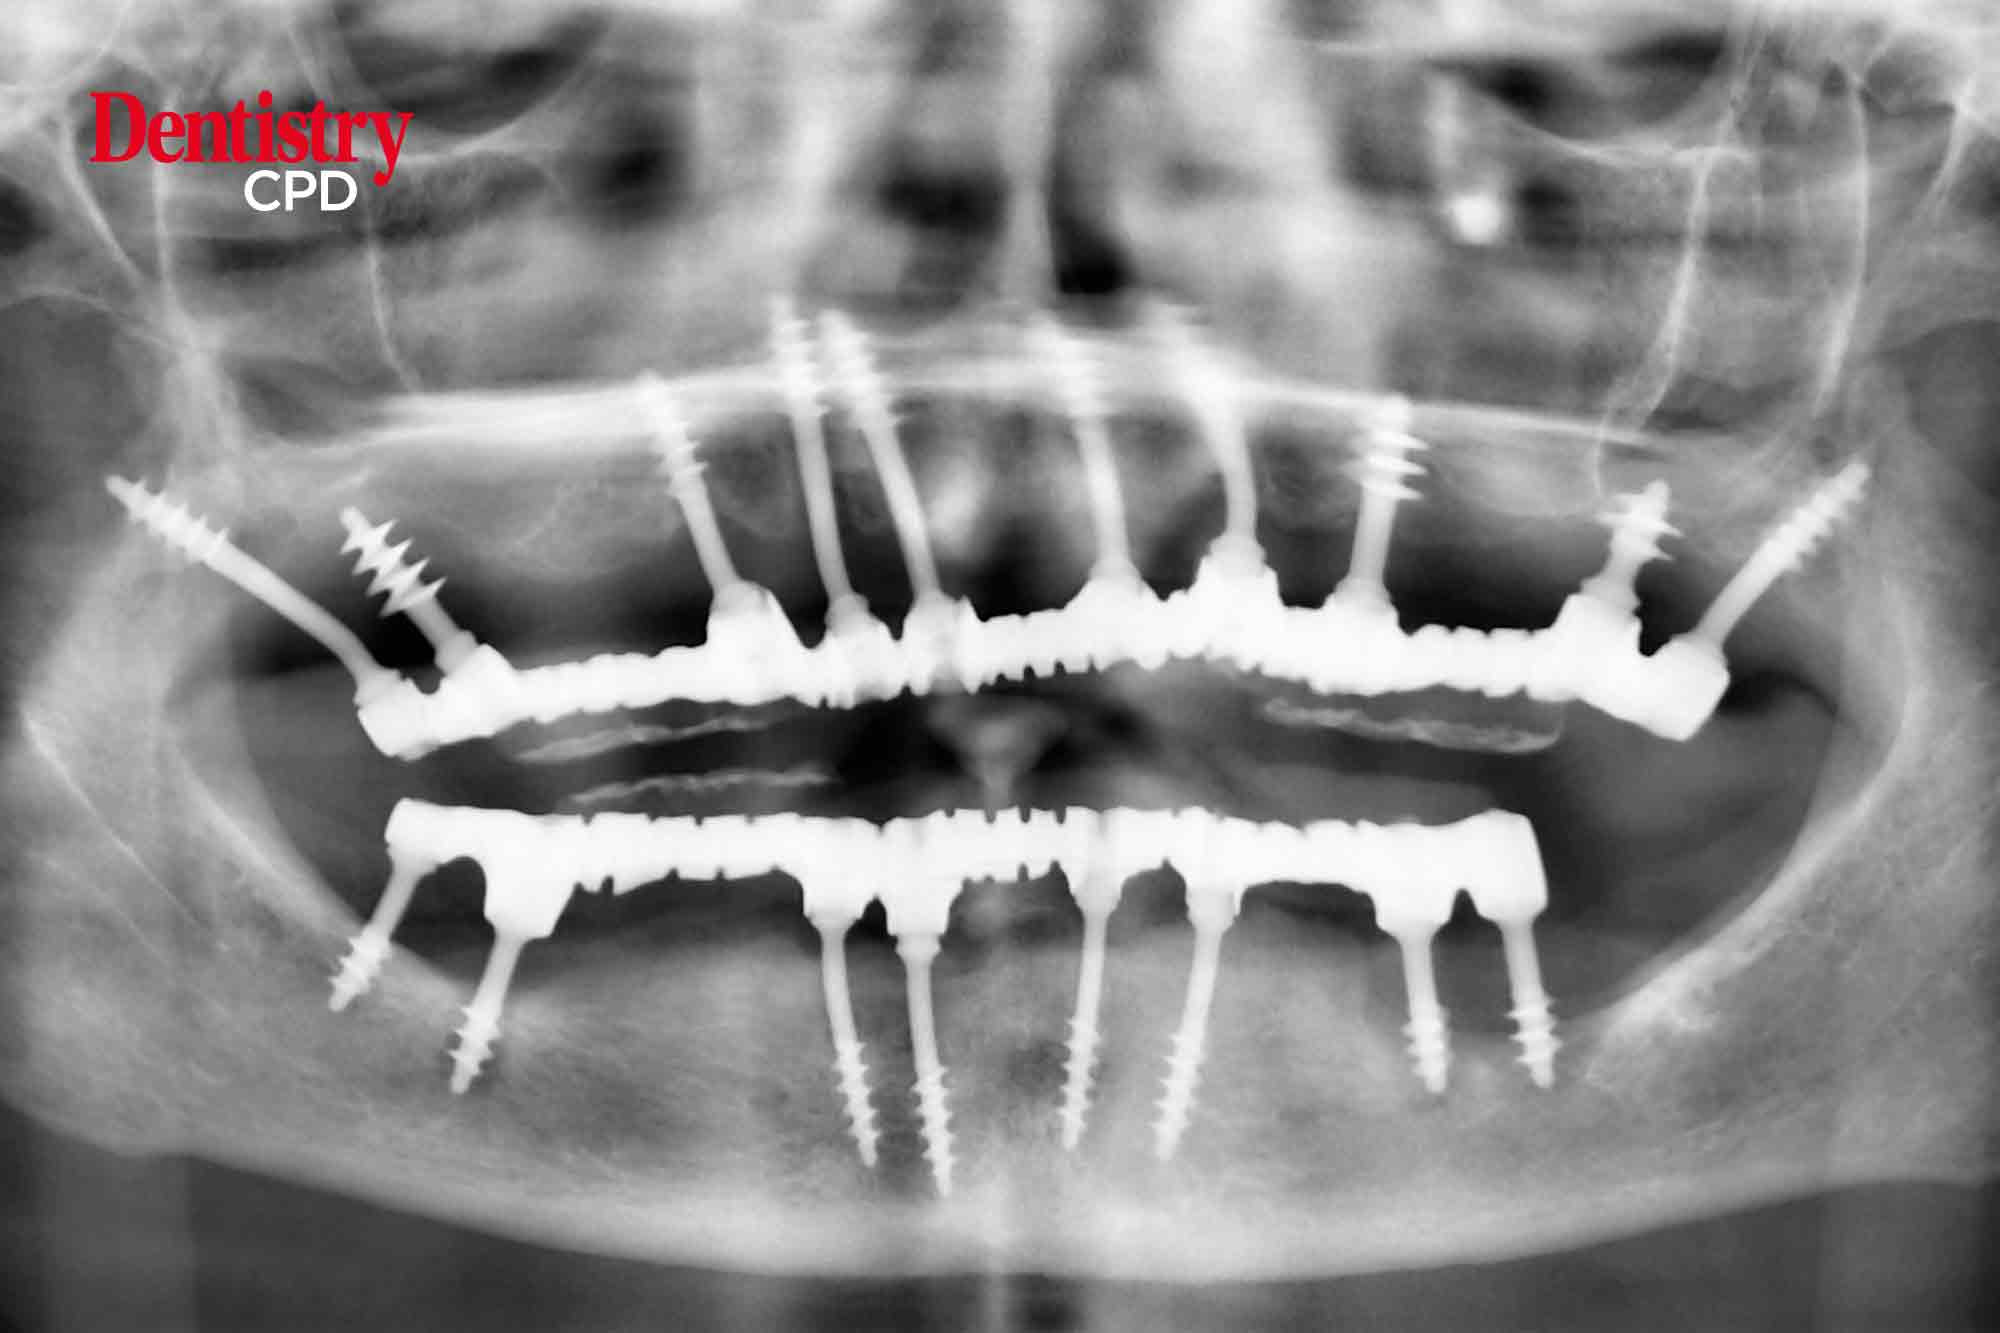

Alex Jones details a complex retreatment case following failed implant treatment undertaken abroad.

To present an immediate full-arch implant case correcting failed implant treatment undertaken abroad